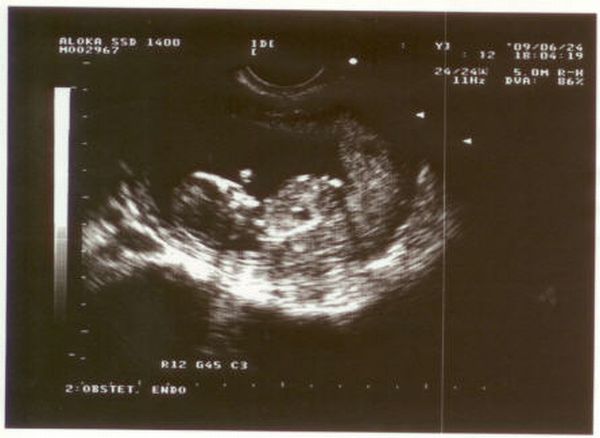

Szilardinho, jók a képek, és gratulálok az eredményhez is!

Uxi, túl sok mindent nem fogsz még látni. Ilyenkor még olyan kis ufók